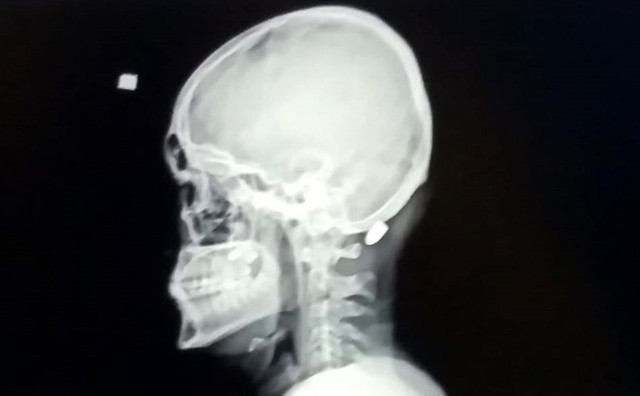

Abone olOlay, dün saat 14.30 sıralarında Karadağ Yaylası'nda meydana geldi. Ali Kuleyin yaylada gezindiği sırada ensesinde acı hissetti. Genç, ensesini arkadaşlarına gösterdi. Kuleyin'in ensesinde mermi çekirdeği olduğunu fark eden arkadaşları, durumu sağlık ekiplerine haber verdi.

Gelen sağlık ekiplerince ilk müdahalesi yapılan Kuleyin, ambulansla Vakfıkebir Devlet Hastanesi'ne kaldırıldı. Mermi, ameliyatla çıkarıldı. Sağlık durumunun iyi olduğu bildirilen Ali Kuleyin, tedavisinin ardından taburcu edildi.